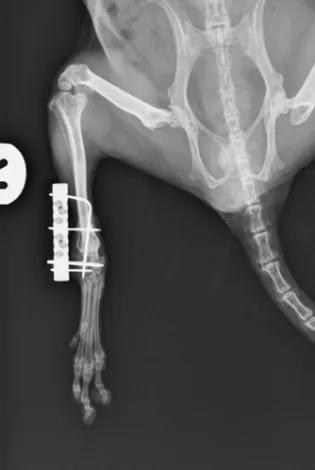

We offer a referral service for complex and challenging cases. As well as our general practice clinic, we offer a referral service for veterinary surgeons who may have more complex or challenging cases.Referral requestsReferral requests must be made by the primary care veterinary surgeon and can be requested by following the link below for our referring vets form. We will always provide an estimate of costs for referral consultation, investigations and treatments, so that referring vets and clients are aware of the likely costs of veterinary care, before attending an appointment.Advice requestsOur team offers a complimentary advice service for referring vets where we can help support them, while they retain responsibility for the case management. Advice can be requested by following the link below for our referring vets form. Referring vets form Albino ferret receiving a conscious abdominal ultrasound scan. Cloacoscopy in a Hermans tortoise An anaesthetised rabbit with venous access via the marginal ear vein, an endotracheal tube has been placed to maintain and protect the airway and pulse oximeter on the tongue. We also use Doppler, capnograph and thermometer probes as key parts of our anaesthetic monitoring. A radiograph of the hindlimb of a chinchilla following a fracture repair. The fracture was stabilised with the help of a very small external fixator. The chinchilla went on to make a full recovery. A rabbit receiving oral medication by one of our qualified Veterinary Nurses. Related LinksUpdates for referring vets Hospital for Small Animals The Royal (Dick) School of Veterinary Studies Contact details Work: 0131 650 7650 Email: hfsareception@ed.ac.uk Web: what3words ///consults.pavement.bulky This article was published on 2024-09-02